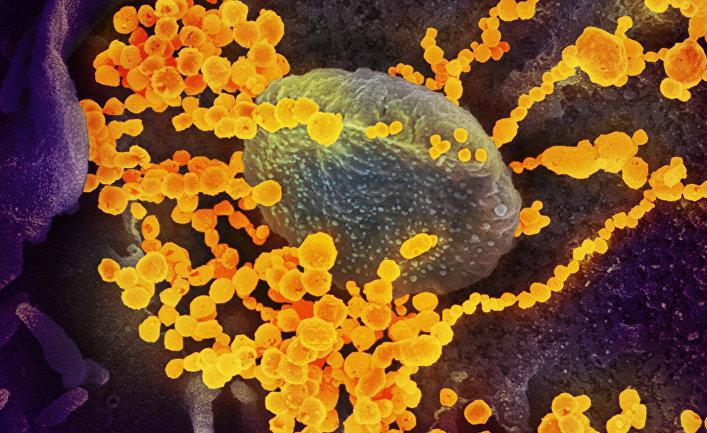

Коронавирус продолжает мутировать, и этот процесс ускоряется за счет многочисленных носителей вируса в разных уголках мира, пишет автор. Она предупреждает: совсем скоро случаи повторного заражения могут стать ужасающей реальностью. Но с чем именно это связано? С мутацией вируса или «странными» сбоями работы иммунной системы? передает UfoSpace.net со ссылкой на inosmi.ru.

Поскольку коронавирус продолжает мутировать, — а этот процесс ускоряется с помощью огромного количества вирусоносителей в разных уголках мира — совсем скоро случаи повторного заражения могут стать ужасающей реальностью. На протяжении большей части 2020 года общепризнанным считался единственный вариант повторного заражения коронавирусом, известным как OG SARS-CoV-2. Не так давно ученые установили несколько случаев, когда выздоровевшие от covid-19 люди заражались новыми вариантами вируса. К настоящему времени эксперты не пришли к единому мнению относительно классификации этих случаев и не могут отличить их от тех случаев, когда иммунная защита человека исчезала.

Рассмотрим, как ведет себя в этой борьбе противная сторона. Хотя коронавирус мутирует медленнее, чем другие респираторные вирусы, он эволюционирует с головокружительной скоростью. Одно-единственное генетическое изменение не делает вирус невидимым для иммунной системы в целом, но последовательные изменения «внешности» способны полностью переделать его в незнакомца. Получается, что последующие случаи инфицирования связаны не столько с плохой памятью организма, сколько с маскировкой вируса — это подобно разнице между ограблением в случае неисправной системы безопасности и преступлением, успех которого объясняется костюмом, в который был одет мошенник. «Организм полагает, что это кто-то совсем другой», — объясняет Брэндон Огбуну (Brandon Ogbunu), эколог и специалист в области вычислительной биологии из Йельского университета. В конце концов, каждый эволюционирующий вирус может настолько измениться, что новое заражение уже будет не реинфицированием, а отдельным случаем, хотя и связанным с первым случаем инфицирования, — сороральным инфицированием или эпи-инфицированием (после-инфицированием).